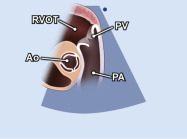

| 2.5. Mặt cắt trục dài cạnh ức qua đường ra thất phải |

||||||||

|

|

Cửa sổ siêu âm cạnh ức

Mặt cắt trục dài cạnh ức Ngửa và xoay đầu dò về phía đường ra thất phải/ |

Đường ra thất phải (RVOT) Van động mạch phổi (PV) Động mạch phổi (PA) |

|||||